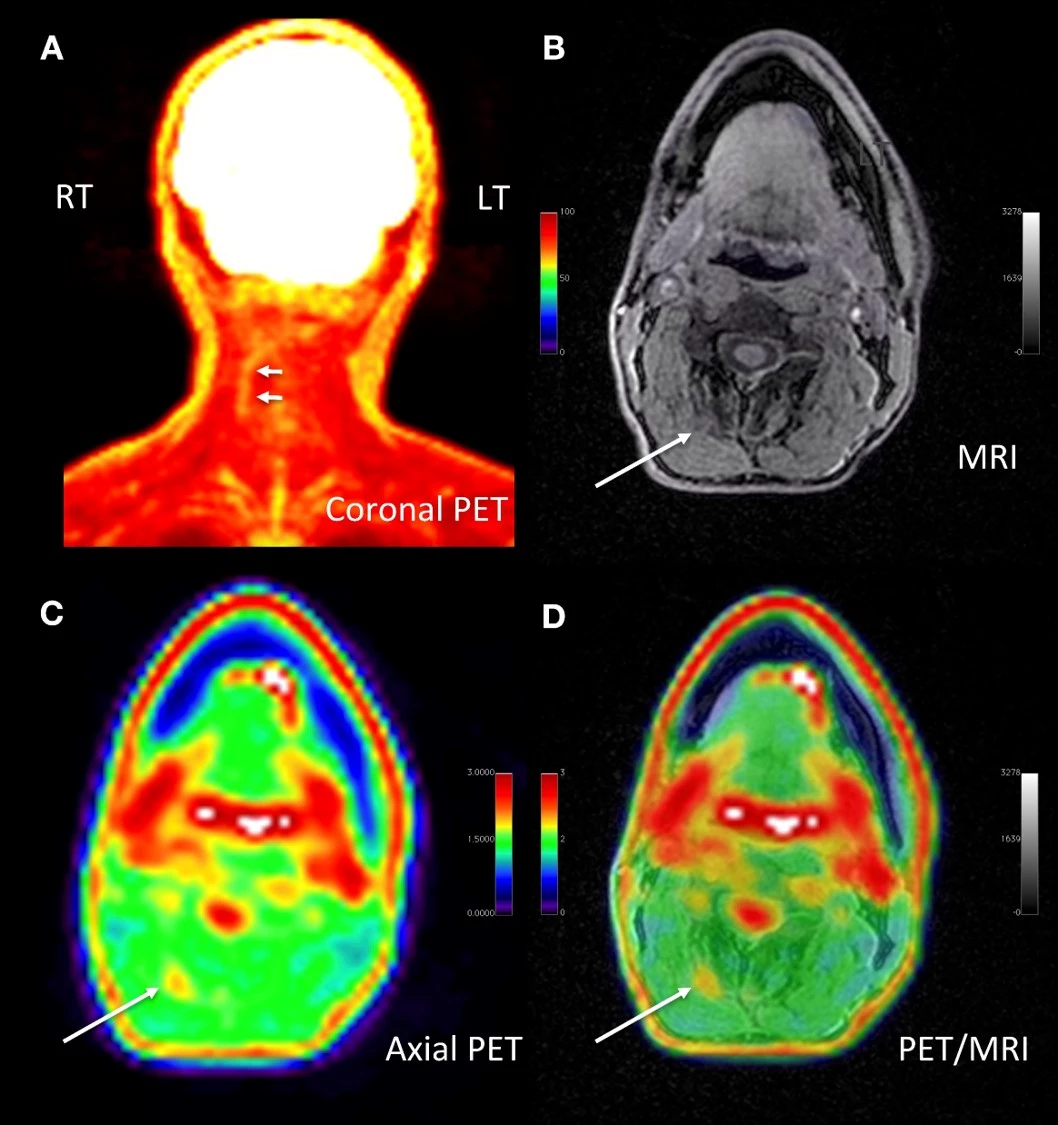

The researchers note one patient, for example, presented with decades of chronic neck pain that was unresolved after multiple treatment options. The scan highlighted, with incredible specificity, a particular location with elevated FDG uptake.

Based on the imaging data a surgeon explored the spot and discovered the source of the chronic pain to be a number of tiny arteries constricting a nerve. Following a quick surgical procedure, known as lysis, the patient reported significant relief to the chronic pain they had suffered for years.